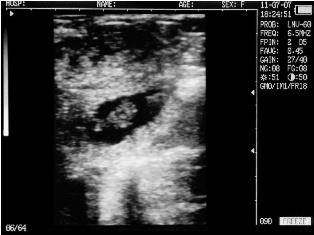

Cow with calf. Deadline - 35 days